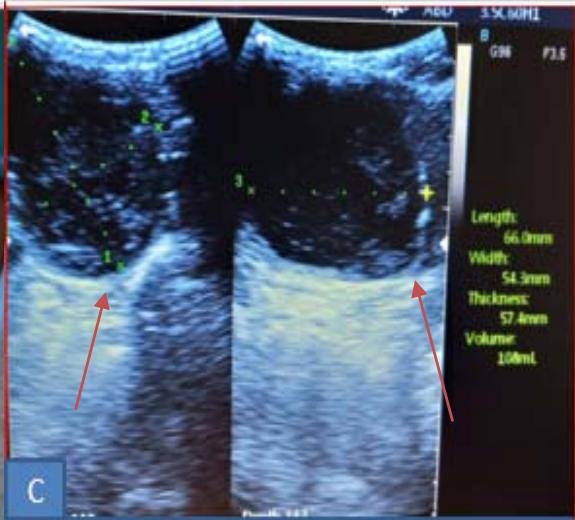

Iconography B: Patient with a 108 ml right isthmo-lobar thyroid hematocele during the first drinking session. A. Materials used before sclerotherapy, B. Image showing a right anterior and lower cervical swelling, Ultra sonographic image: showing a hypoechoic mass dotted around the partitions of 108 ml, D. image showing after ultrasound-guided puncture showing hematic content in the syringe, E. Ultra sonographic image in B mode, showing linear hyper echogenicity of the needle.